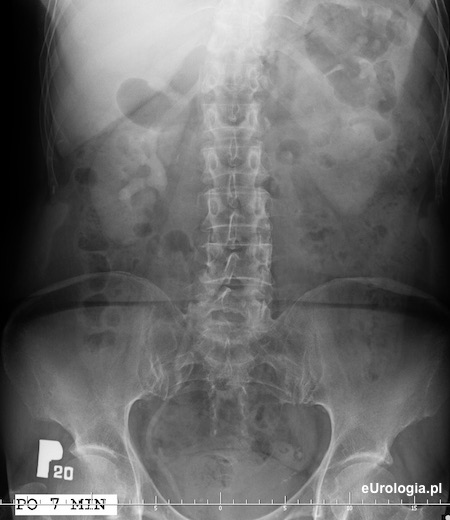

Zdjęcie urograficzne wykonane po 7 minutach od podania kontrastu. Na zdjęciu uzyskano zakontrastowanie układu kielichowo-miedniczkowego nerki prawej i zakontrastowanie moczowodu prawego. Po stronie lewej słabo widoczny nefrogram.